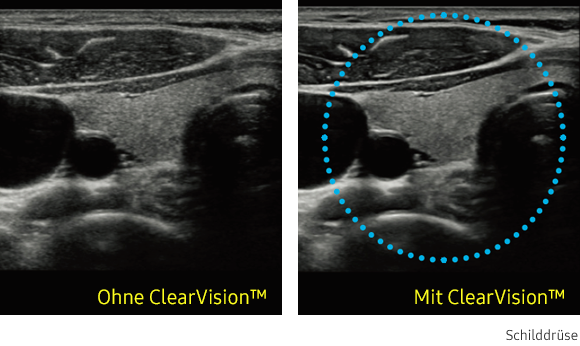

ClearVision

Der Rauschunterdrückungsfilter verbessert die Kantendarstellung und schafft schärfere 2D-Bilder für eine optimierte Diagnoseleistung. Die Integration dieser spezialisierten Samsung-Technologie führt zu einer bemerkenswerten Verbesserung der Bildqualität. Darüber hinaus bietet ClearVision anwendungsspezifische Optimierungsmöglichkeiten und eine erweiterte zeitliche Auflösung im Live-Scan-Modus.

Ultraschallbild Schilddrüse links ohne ClearVision und rechts mit ClearVision von Samsung. Ultraschallbild Schilddrüse links ohne ClearVision und rechts mit ClearVision von Samsung. Ultraschallbild Schilddrüse links ohne ClearVision und rechts mit ClearVision von Samsung. Ultraschallbild Schilddrüse links ohne ClearVision und rechts mit ClearVision von Samsung.